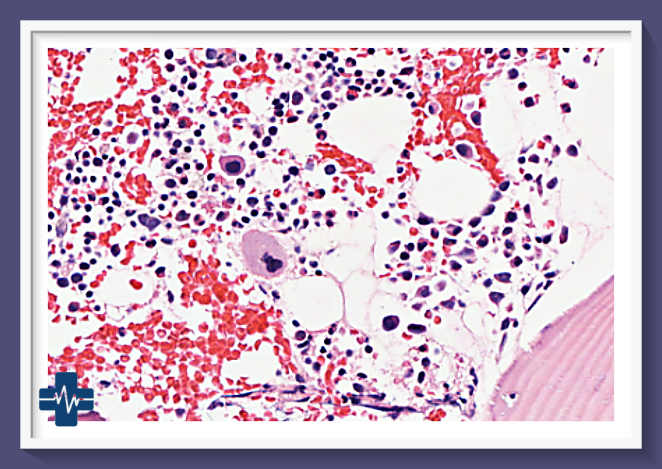

골수암, 특히 급성 및 만성 골수성 백혈병은 혈액암의 한 유형으로, 골수에서 비정상적인 백혈구가 과도하게 생산되는 질환입니다. 이 질환은 골수의 정상적인 기능을 방해하여 다양한 신체적 증상을 유발하며, 진단과 치료가 시급한 중대한 건강 문제입니다.

골수암, 특히 다발성 골수종과 급성 골수성 백혈병은 혈액암의 주요 유형으로, 골수에서 비정상적인 혈액 세포의 과도한 증식을 특징으로 합니다. 이러한 암의 생존율은 다양한 요인에 의해 영향을 받으며, 최근 몇 년간 치료법의 발전으로 인해 개선되고 있는 추세입니다.